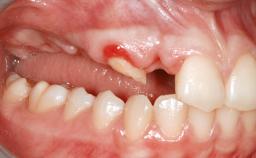

Her chief complaint was her inability to masticate efficiently due to the recent loss of her mandibular second premolars and first molars bilaterally. She expressed a desire for fixed prostheses in the shortest possible time due to her advanced age, requesting that replacement teeth should look as natural as possible. She was otherwise comfortable and not experiencing any symptoms from her teeth.

Placement Protocol Early or late implant placement